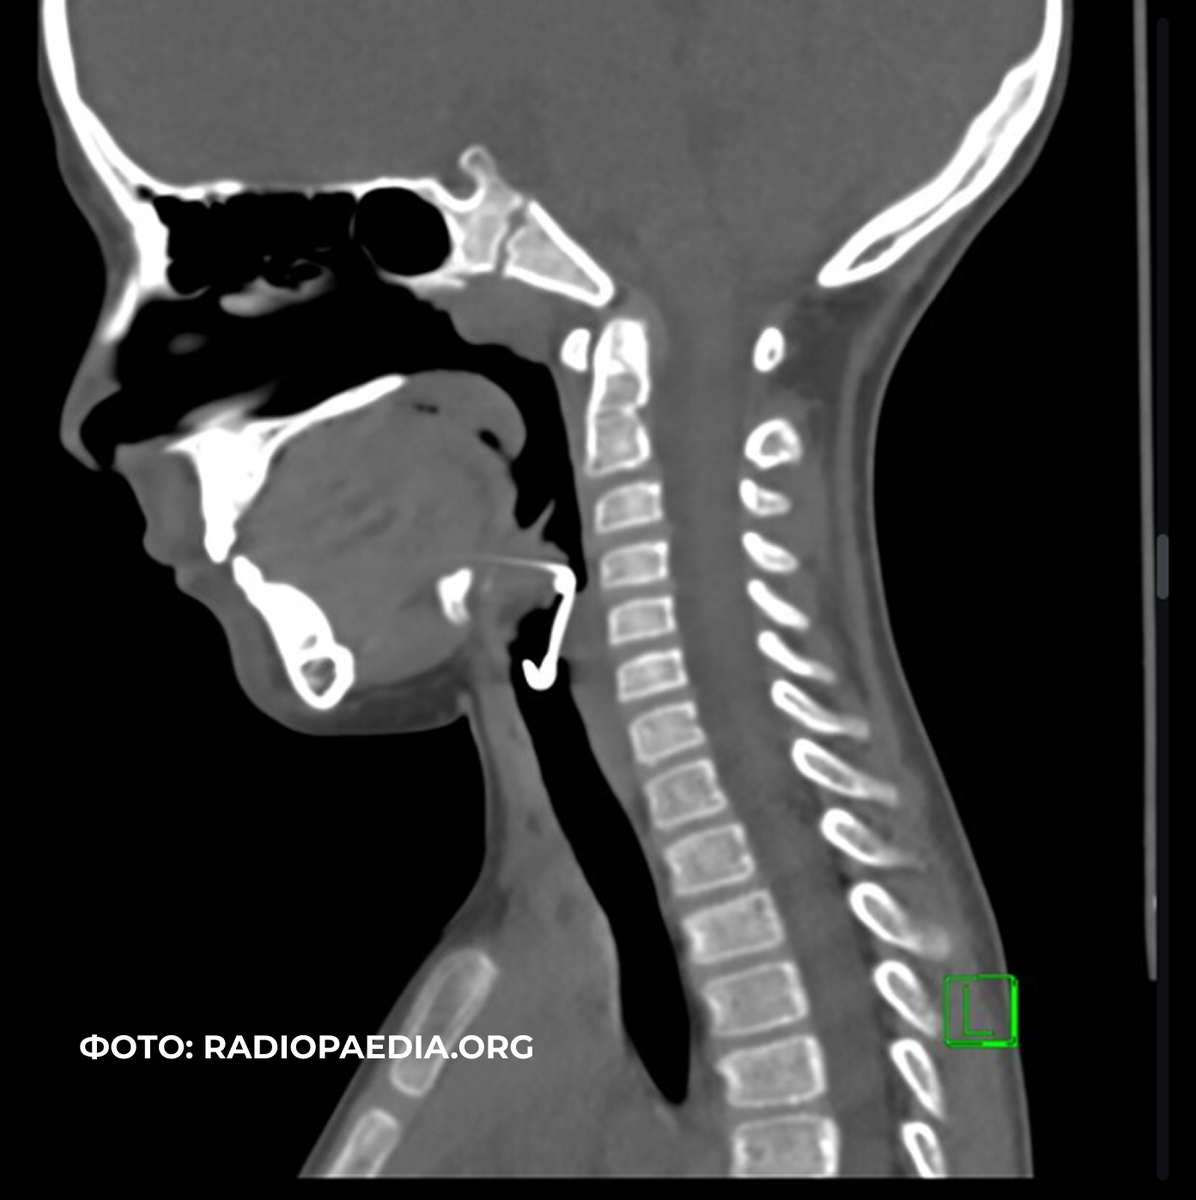

- Возможно, понадобится рентгенография, КТ или МРТ мягких тканей шеи.